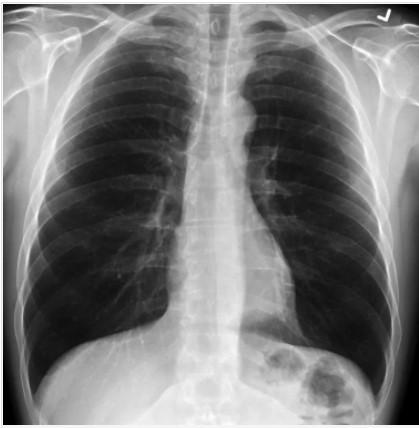

Медик зазначила, що легені пацієнтів після COVID-19, виглядають набагато гірше, ніж навіть у курців. На рентгенівському знімку здорового пацієнта було багато чорного простору, яке демонструвало, що людина могла вдихати нормальну кількість кисню.Легені здорової людини